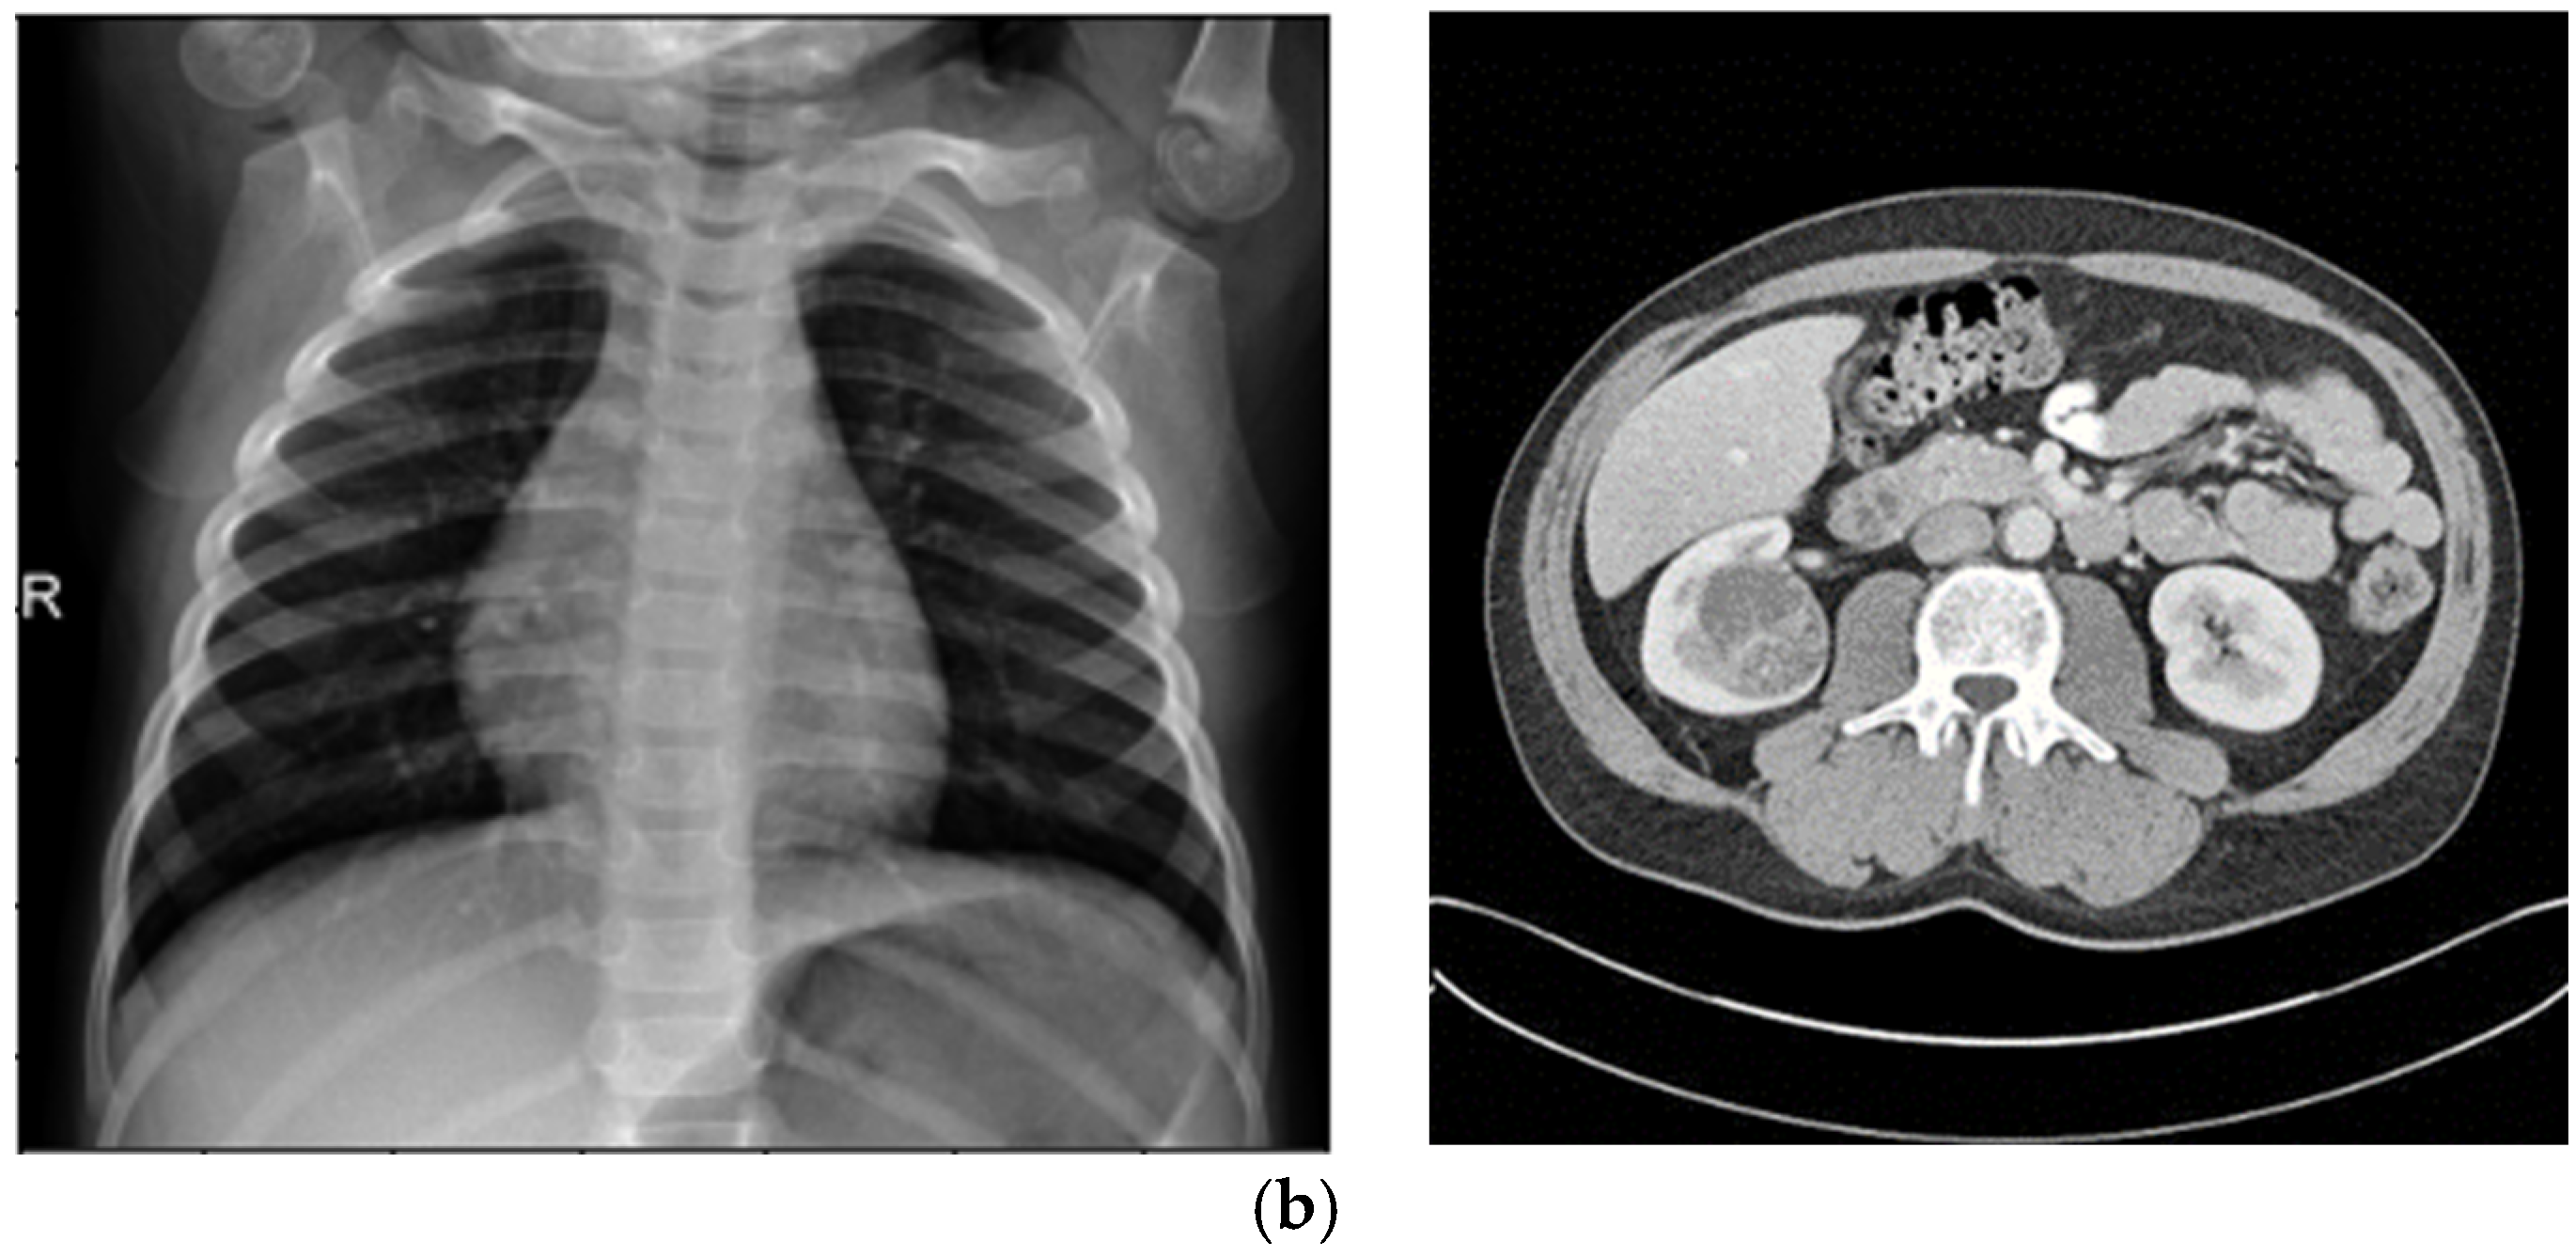

4.1.1. KiTS19

210 training and 90 test instances of 3D CT scans with annotations for kidney and tumor regions make up the Kidney Tumor Segmentation 2019 (KiTS19) dataset, which was obtained from Kaggle. https://www.kaggle.com/datasets/sabahesaraki/kidney-tumor-segmentation-challengekits-19/data (accessed on 15 September 2025).

This dataset serves as a standard for assessing automated segmentation algorithms in clinical settings and is intended for the semantic segmentation of kidneys and malignancies. The CT scans are appropriate for evaluating the enhancement pipeline’s capacity to increase contrast and lower noise in soft tissue areas since they provide comprehensive anatomical structures. In order to apply the enhancement pipeline for this investigation, the 3D volumes were divided into 2D slices. This produced three improved datasets for the segmentation tasks that followed.

4.3.3. Segmentation Performance (KiTS19)

The original dataset (300 cases) and the improved datasets (900 cases total: 300 × 3) were used to train the two CNN models for the KiTS19 dataset. The improved datasets were used to train CCNN, and the fuzzy entropy-based dataset produced the best-performing model (BRISQUE: 23.1). Dice coefficient, accuracy, precision, sensitivity, and recall were used to assess performance. The BRISQUE scores and segmentation accuracy of the three models are contrasted in Table 4.

Both the original and CLAHE-filtered datasets fared worse than the suggested enhancement pipeline. The BRISQUE score of the original KiTS19 dataset was 28.8, but CLAHE raised it to 26.4. Our approach produced better image quality with a lower BRISQUE score of 21.7. The significant influence of our enhancement strategy on segmentation performance was demonstrated by the CCNN model trained on our enhanced dataset, which achieved an accuracy of 0.983, a 2.4% improvement over the CLAHE-filtered dataset (0.959), and a 6.2% improvement over the original dataset (0.921). Figure 5 includes a sample visualization of the segmentation results.